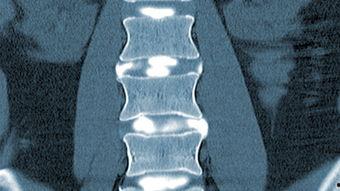

腰椎CT视频,听起来是不是有点高大上?其实,它就是通过CT扫描技术,将腰椎的内部结构清晰地呈现在我们眼前的一种检查方法。那么,它到底能揭示哪些秘密呢?

腰椎管狭窄是指腰椎管内空间变小,压迫神经根或脊髓。腰椎CT视频可以帮助我们判断腰椎管狭窄的程度,为医生制定治疗方案提供依据。

腰椎骨折是老年人常见的疾病,也是导致腰痛的原因之一。腰椎CT视频可以清晰地显示骨折部位、程度以及是否伴有其他并发症。